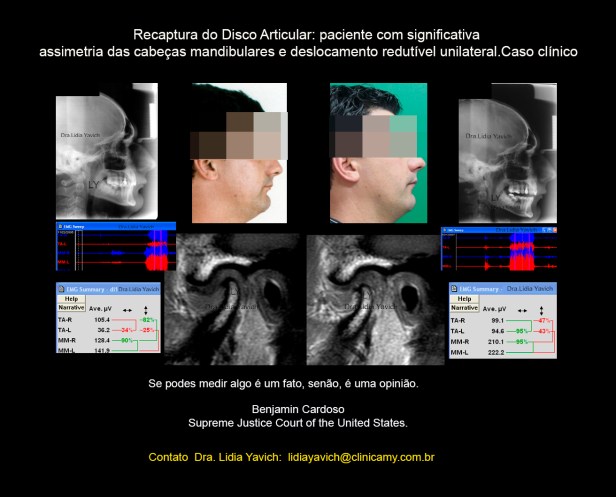

Radiografia panorâmica do paciente antes do tratamento.

Assimetria das cabeças mandibulares.

Laminografia da ATM em oclusão habitual em fechamento e abertura.

Assimetria entre a cabeça mandibular direita e esquerda do paciente. Aplainamento superior de ambas as cabeças mandibulares e alteração do eixo de crescimento de ambos os côndilos mandibulares.

Neste exame cinesiográfico é registrada abertura e fechamento do paciente em vista sagital e frontal e o gráfico de velocidade.

O paciente tem uma abertura de 40 mm, e frontalmente precisa fazer um desvio para o lado esquerdo para conseguir abrir a boca.

A velocidade de abertura e fechamento é pobre, o paciente apresenta bradicinesia.

Neste registro eletromiográfico do paciente em oclusão habitual é gritante a diferença entre os temporais anteriores direito e esquerdo.

Existe quase 70 por cento de diferencia entre o temporal esquerdo e o direito em oclusão máxima habitual.

O temporal anterior direito consegue gerar 105 microvoltios na faixa analisada já o temporal anterior esquerdo consegue gerar só 36 microvoltios, na mesma faixa.

RNM: Ressonância Nuclear Magnética do paciente. Corte selecionado.

1 corte sagital da ATM ESQUERDA em boca fechada antes do tratamento. Deslocamento redutivel do disco articular.

2 -A mesma imagem com realce de cores.

3 -corte sagital da ATM ESQUERDA em boca aberta antes do tratamento.

4– A mesma imagem com realce de cores.  RNM: Ressonância Nuclear Magnética do paciente. Corte selecionado. Corte sagital da ATM DIREITA em boca fechada antes do tratamento.

RNM: Ressonância Nuclear Magnética do paciente. Corte selecionado. Corte sagital da ATM DIREITA em boca fechada antes do tratamento.

Disco articular em posição habitual Corte sagital da ATM DIREITA em boca aberta antes do tratamento.

Registro eletromiográfico do paciente em oclusão neuromuscular fisiológica com o dispositivo em boca: os temporais anteriores direito e esquerdo estão equilibrados.

O registro inicial em oclusão habitual registrava quase 70 por cento de diferencia entre o temporal esquerdo e o direito em oclusão máxima habitual.

Registros eletromiográficos comparativos: o superior em oclusão habitual e o inferior em oclusão neuromuscular fisiológica com o DIO (dispositivo intraoral) em boca.

Corte sagital externo da ATM esquerda em boca fechada antes do tratamento mostrando o DESLOCAMENTO DO DISCO ARTICULAR e a RECAPTURA DO DISCO ARTICULAR após o tratamento.

Controle comparativo da segunda ressonância nuclear magnética após a primeira fase do tratamento. Serão postadas as imagens da ATM esquerda, que apresentava o deslocamento do disco articular.

A ATM do lado direito não apresentava deslocamento, só as diferencias estruturais entre as duas cabeças mandibulares.

Corte sagital externo da ATM esquerda em boca fechada antes do tratamento mostrando o DESLOCAMENTO DO DISCO ARTICULAR e a RECAPTURA DO DISCO ARTICULAR após o tratamento.

Corte sagital interno da ATM esquerda em boca fechada antes do tratamento mostrando o DESLOCAMENTO DO DISCO ARTICULAR e a RECAPTURA DO DISCO ARTICULAR após o tratamento.

Corte sagital interno da ATM esquerda em boca fechada antes do tratamento mostrando o DESLOCAMENTO DO DISCO ARTICULAR e a RECAPTURA DO DISCO ARTICULAR após o tratamento.